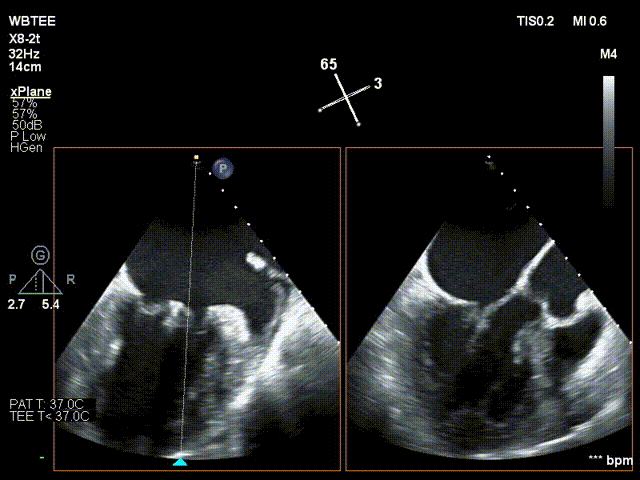

反复测试二尖瓣钳夹的稳定性,超声复查提示二尖瓣夹内侧反流有效改善,外侧仍有部分反流,平均跨瓣压差2mmHg,肺静脉收缩期逆流频谱恢复正向,傅国胜教授团队与超声影像团队充分沟通讨论,计划在二尖瓣夹外侧再置入第二枚二尖瓣夹,遂精准释放第一个二尖瓣夹。

傅国胜教授继续在食道超声影像引导下进行高难度操作,在第一个二尖瓣夹外侧再置入第二枚二尖瓣夹NTR。

再次反复测试第二枚二尖瓣钳夹的稳定性,超声复查提示二尖瓣反流明显改善,平均跨瓣压差4mmHg。